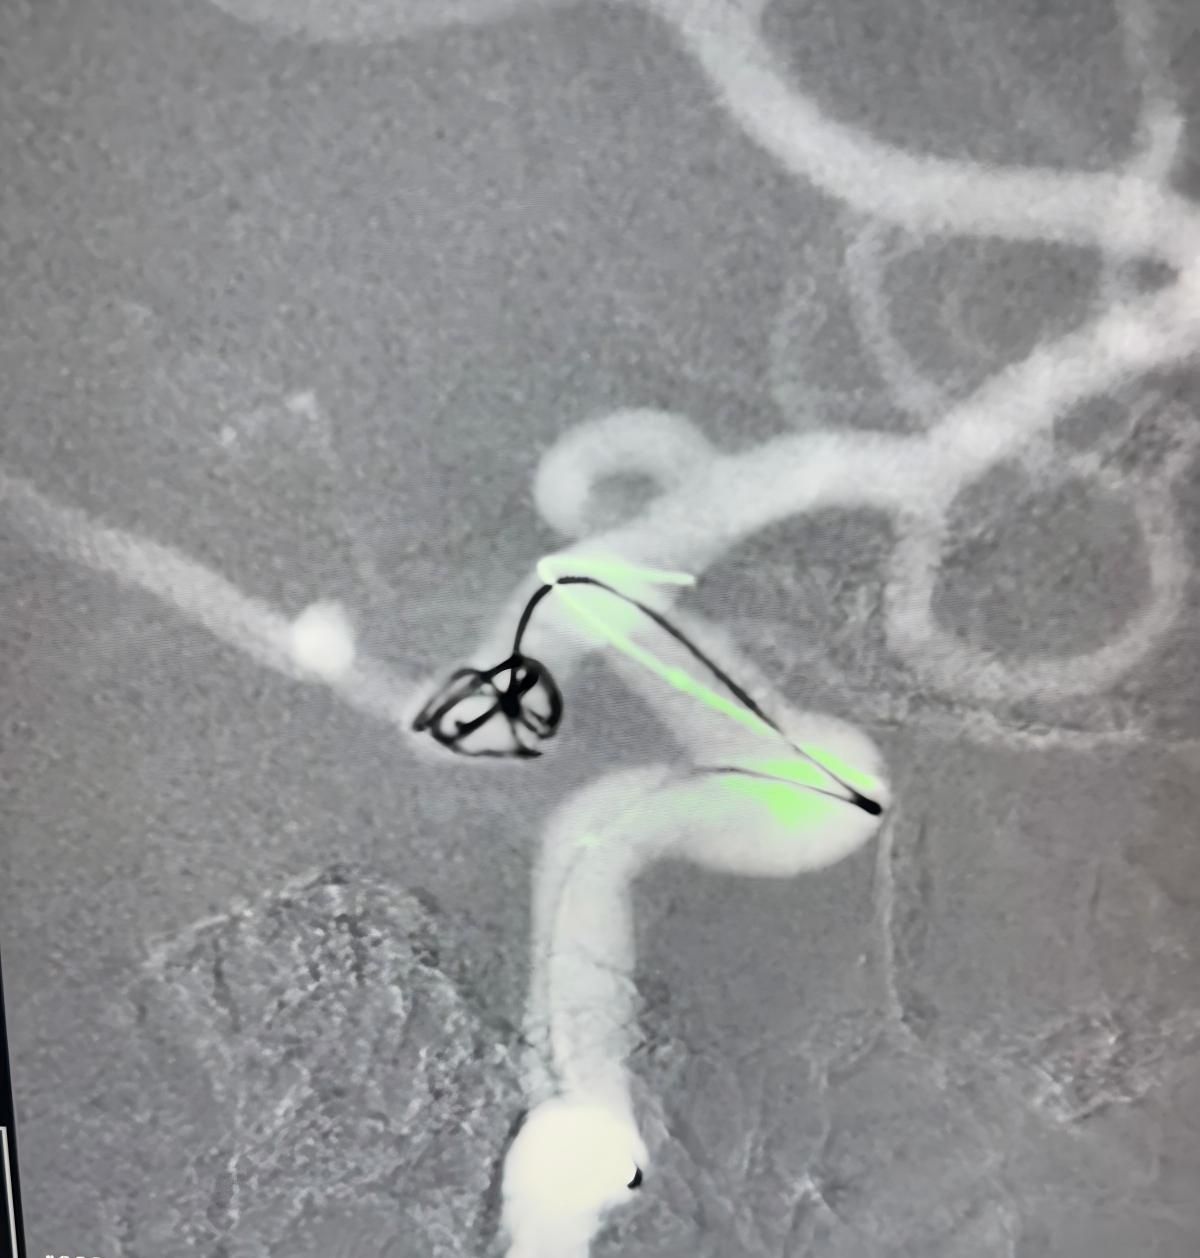

Nos complace compartir un procedimiento exitoso reciente en Clínica Alma Mater, Medellín, realizado por el Dr. Jorge Mutis.

El tratamiento utilizó el Nuva®Desvedor de flujo (TJED-D 5.0-14), Perdenser®Bobina 3D, y el paso de tierra®Microcatéter (TJMC18 Plus) para un aneurisma de arteria comunicante posterior.

Dr. Mutis destacó la excelente visibilidad del dispositivo y señaló que la recuperación fue suave. Expresó su gran satisfacción por el resultado final.